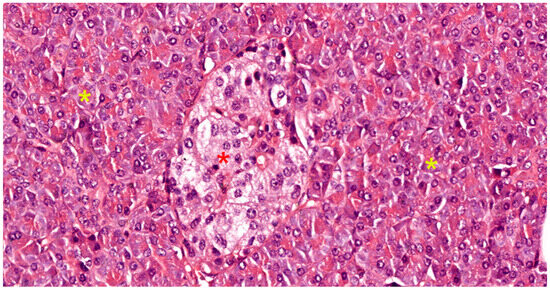

5. Histopathology of Acute Pancreatitis